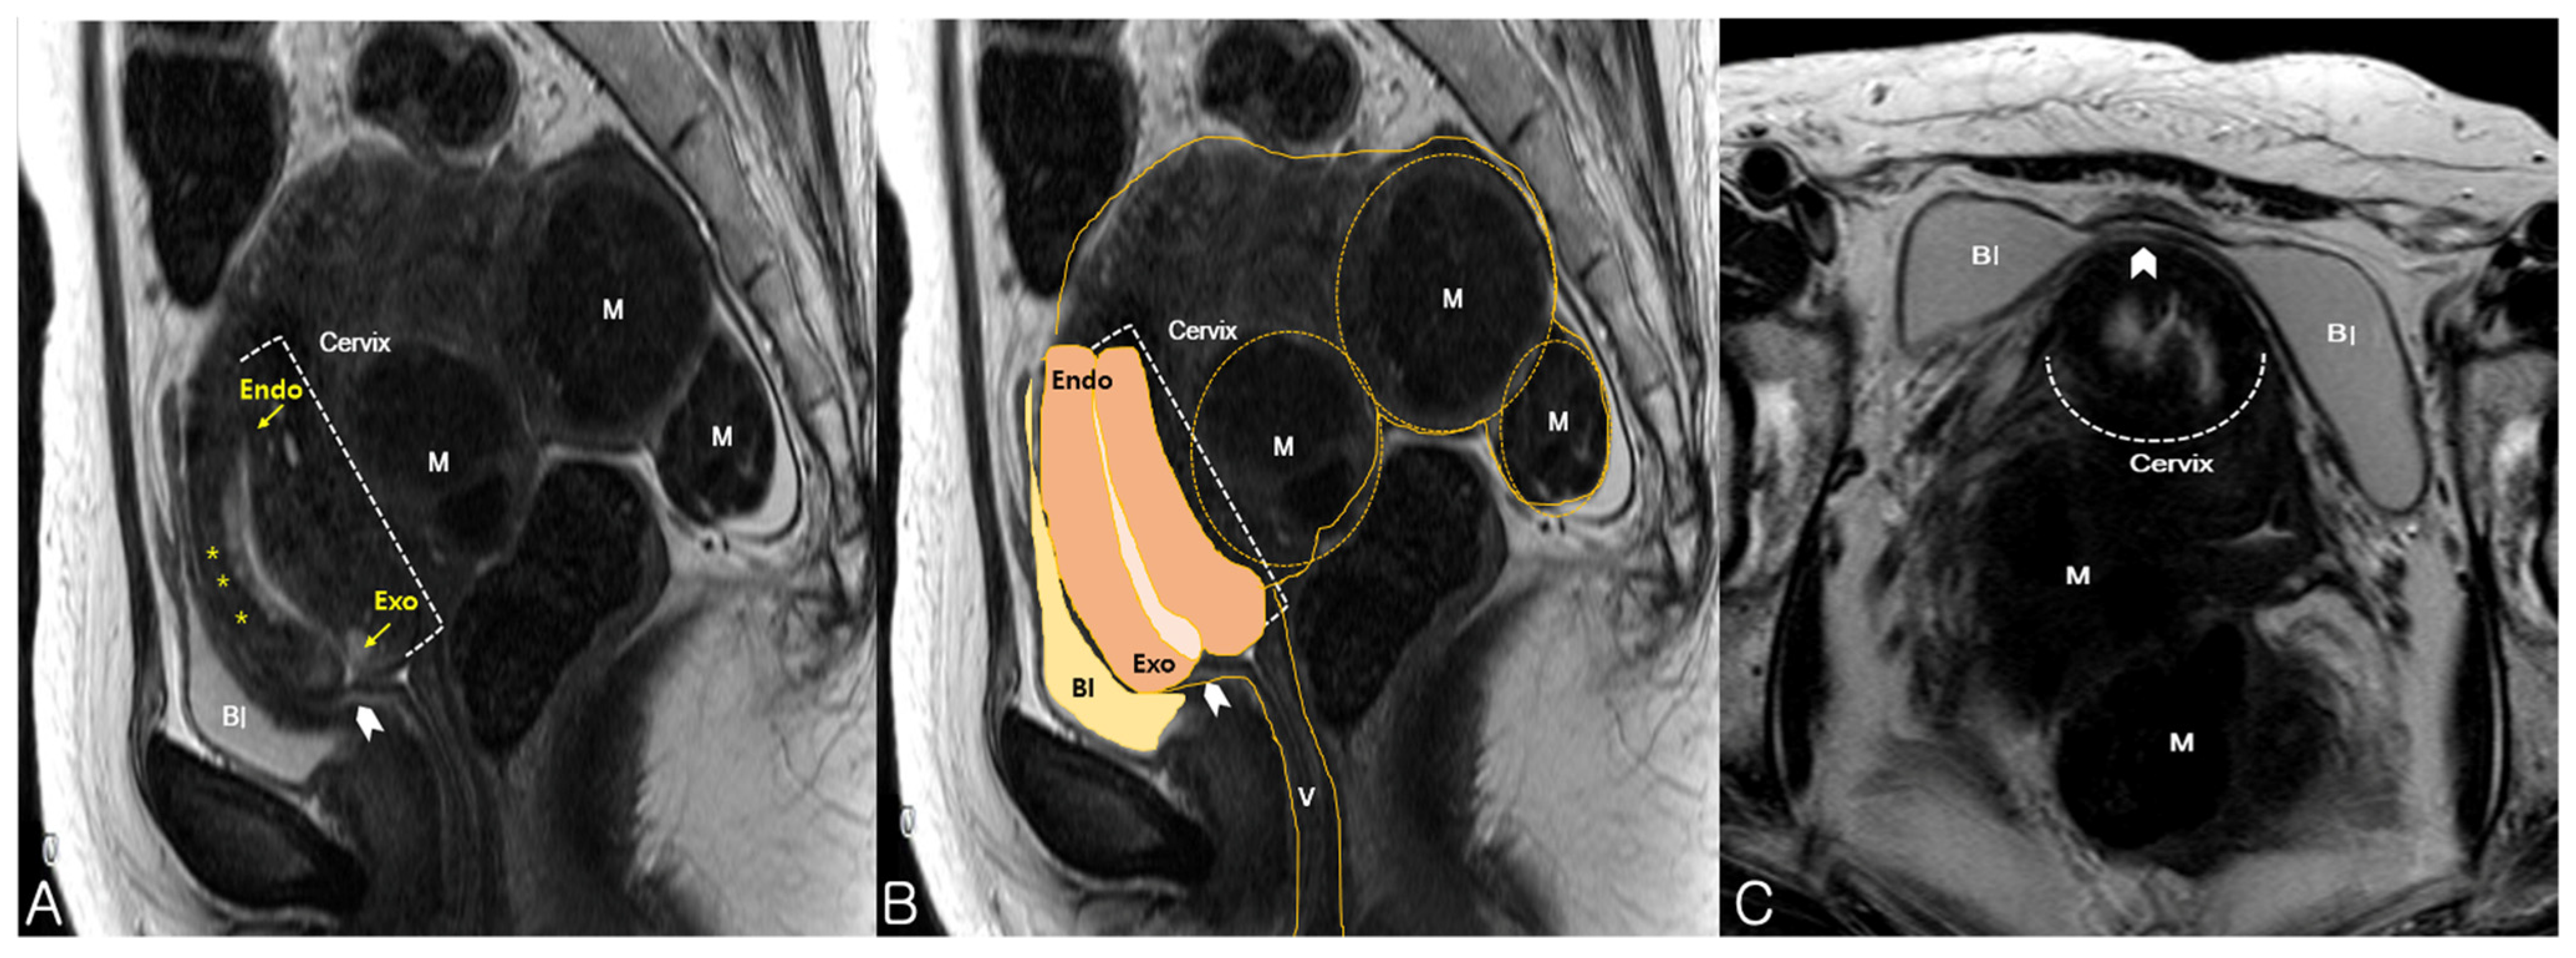

On pelvic examination, the uterine cervix was displaced anteriorly. Therefore, the cervix was out of reach and could not be exposed on vaginal examination. Sonography revealed an 18 × 7-cm retroflexed fibroid uterus and an elongated uterine cervix (Figure 1A). Translabial sonography revealed that the urethra and the bladder neck were compressed by an extremely retroverted cervix (Figure 1B). In most cases, the axis of the cervix is usually perpendicular to the sonographic probe, but in this case, it was nearly horizontal to the translabial sonographic probe. The elongated ventrocranially displaced uterine cervix was compressing the urinary bladder. MRI showed this relationship between the cervix and the bladder more clearly by revealing an elongated cervix compressing the urinary bladder neck (Figure 2A) as the incarcerated uterus lifted the cervix and fixed it. In addition, the bladder, which was hourglass-shaped, was completely compressed by the cervix (Figure 2C). Manual reduction for the management of the incarcerated uterus was unsuccessful. However, the patient was able to self-void several times immediately after the procedure, clearly suggesting that the prolonged urinary obstruction was caused by the incarceration. Thus, we performed a hysterectomy to treat the uterine incarceration.

Figure 2. Magnetic resonance imaging findings. (A) Adenomyotic uterus with multiple myomas (M). The cervix was elongated and displaced ventrocranially, and compressed (arrowhead) the neck of the urinary bladder (Bl), as observed on mid-sagittal view; Elongated endocervical canal with high signal intensity is clearly visible with endocervical glands (asterisks); (B) A mid-sagittal view revealed an 18 × 7-cm sized, retroverted uterus with myomas (M), trapped in the pelvis. The urinary bladder (Bl) was compressed by the elongated cervix and vagina (V); (C) An axial view revealed a deformed bladder shape (arrowhead), dumbbell-shaped in this case, a clue that can be helpful in detecting an incarceration. Endo, endocervix; Exo, exocervix.